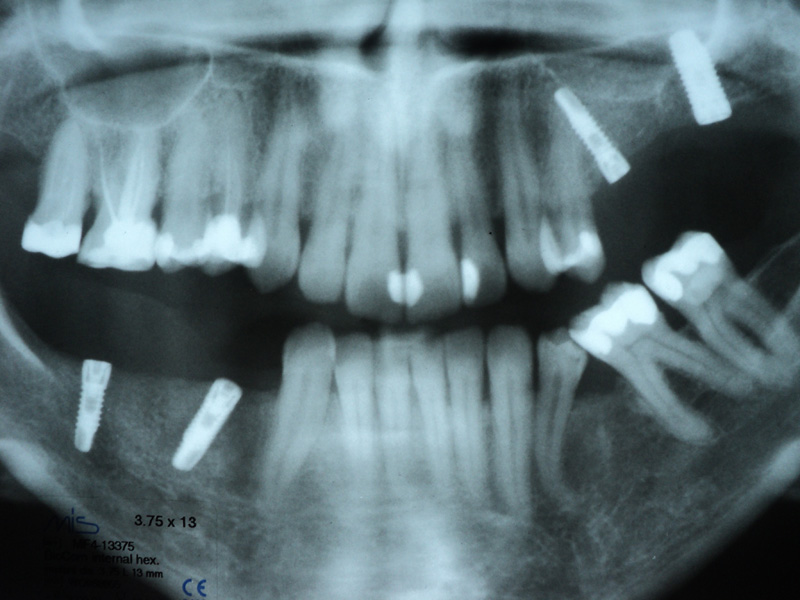

Implante - Galerie Foto

Caz I